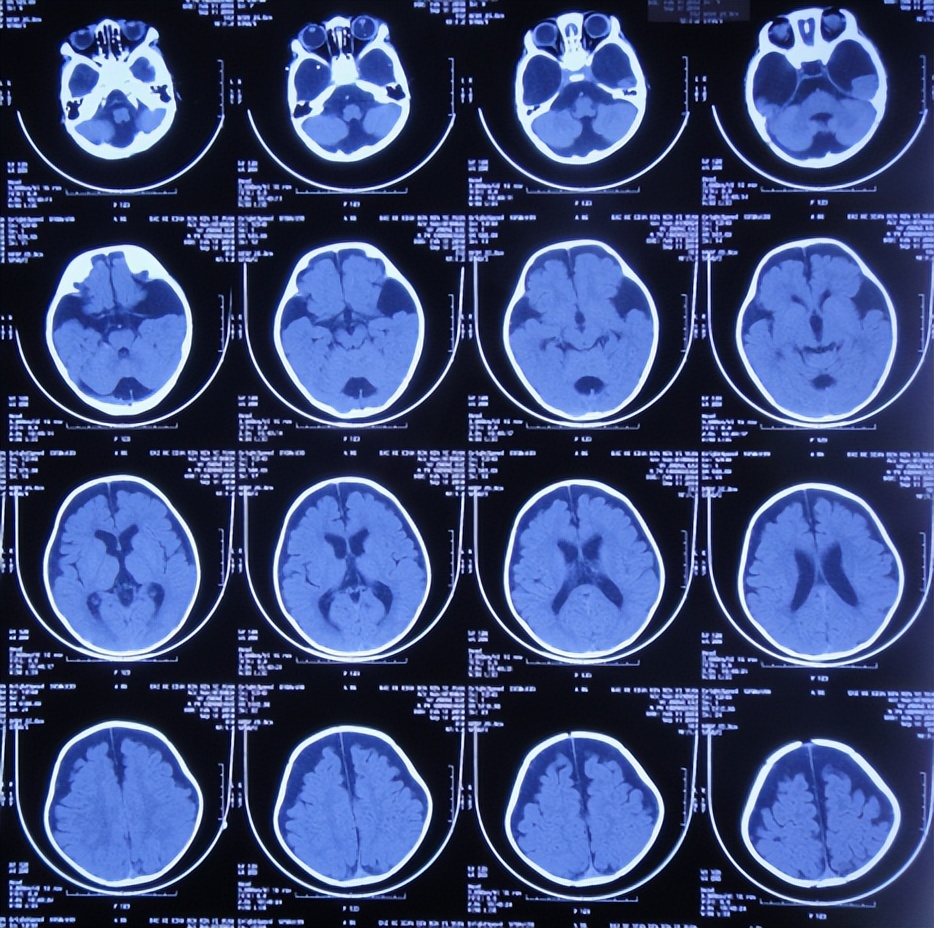

患儿2018年2月份,早产1月,剖宫产出生,出生后未见异常;患儿3个月大起,家属发现患儿头围较同龄幼儿大点,未给予重视;直到7个月大时,因发育迟缓自己不能坐,且头围进行性增大,于2018年9月11日,至当地第1家医院陕西省西康市白河县某医院,检查头颅CT发现双颞叶蛛网膜囊肿、脑积水( 图-1 )。

图-1: 2018年9月11日头颅CT